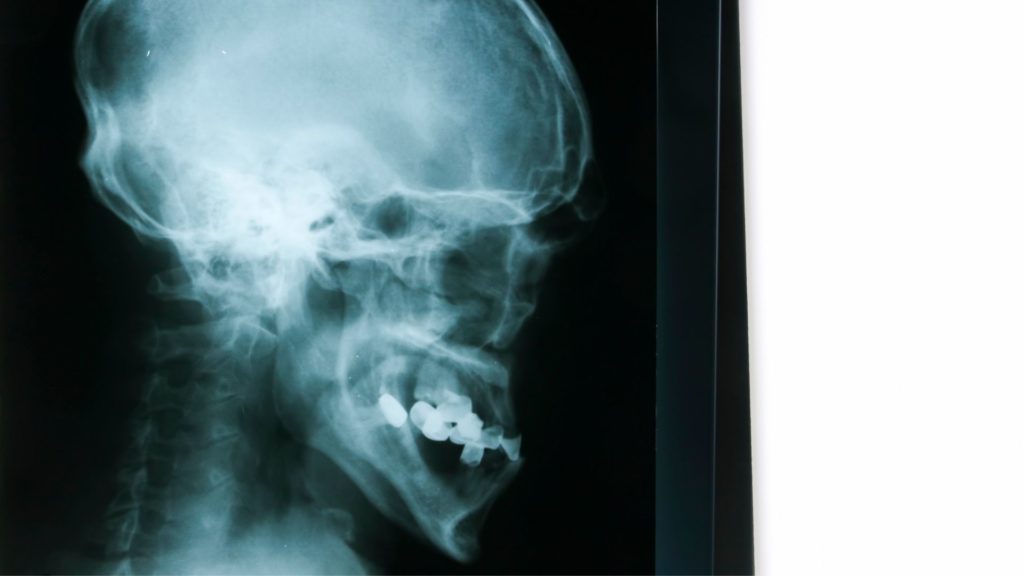

Imagen Dental Intraoral. La tecnología en el campo odontológico ha ido evolucionando a lo largo del tiempo ayudando tanto al odontólogo como a los pacientes a obtener mejores diagnósticos en menor tiempo y a mayor alcance de todos.